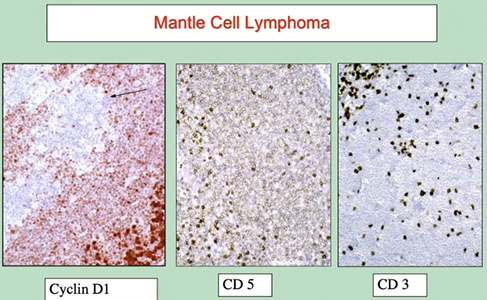

Thioflavin S (fluorescent scope needed)

IHC for Ig light chains, P component (found in most forms of amyloid), Amyloid A

Has become more and more routine to analyze amyloid with mass spec

- becoming the gold standard for amyloid typing

- IHC classification has well-known errors

- Serious consequences!!!